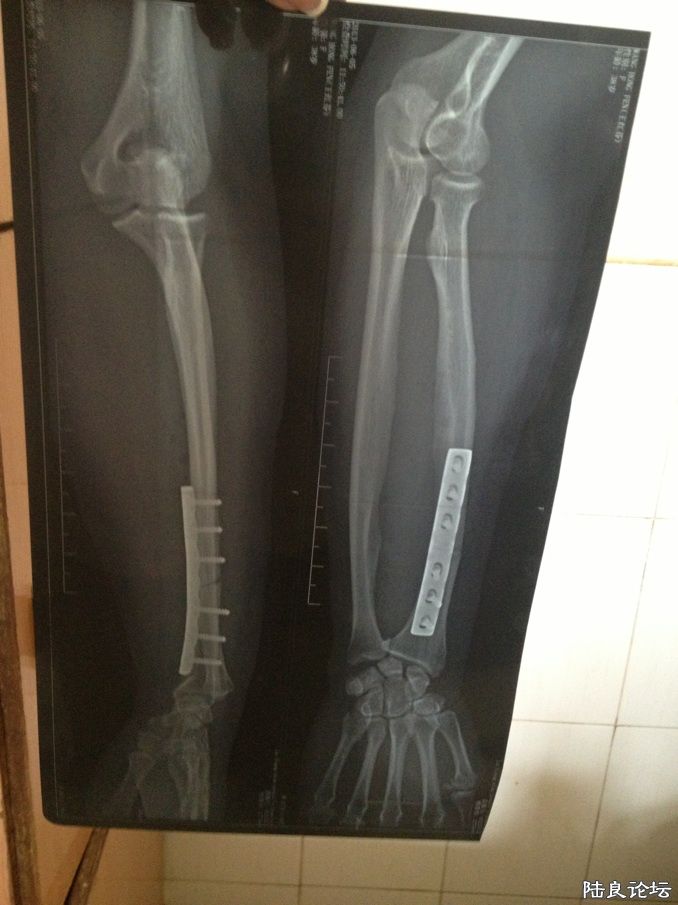

现在打着钢针

现在打着钢针 看着都疼